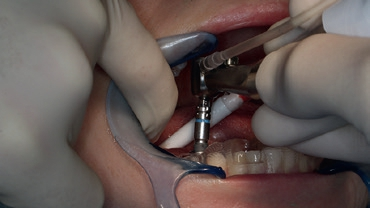

Obwohl ursprünglich als Sofortimplantation geplant, erfolgten die schonende Extraktion (Abb. 3) und die Implantation im Abstand von einer Woche. Das Ziel war es, die apikale Ostitis mit kurz vor dem OP-Termin beginnender bukkaler Schwellung abheilen zu lassen und eine ausreichende Entzündungsfreiheit zu erreichen (Abb. 7). Beim Einsetzen des Implantats kam die Bohrschablone zum Einsatz. Um die Lagestabilität der Schablone zu gewährleisten, war es wichtig, diese ausreichend groß zu dimensionieren (Auflage Zahn 33 bis 46); Sichtfenster ermöglichen es dabei, die planmäßige und vollständige Auflage der Schablone auf dem Zahnbogen jederzeit zu kontrollieren.

Nach der geführten Implantatbettaufbereitung wurde das Astra Tech Implant System EV 4,8C × 13 mm durch die Hülse hindurch mit Höhenanschlag in seine geplante Position inseriert (Eindrehmoment final: 45 Ncm) (Abb. 8 bis 10). Die Lage des Implantats wurde mit einer intraoralen Röntgenaufnahme postoperativ überprüft (Abb. 11). Es folgte die digitale Abformung mit der CEREC Omnicam: Um die Implantatposition exakt zu übertragen, wurde ein Scanbody platziert (Abb. 12). Der dabei erzeugte Scan wurde für das präzise Design eines Provisoriums mit der Abformung des Milchzahnes überlagert und im Anschluss gefräst (Abb. 13). Das Kunststoffprovisorium wurde mit der dazugehörigen TiBase verklebt (Multilink Hybrid Abutment, Ivoclar Vivadent). Zuvor wurden sowohl die TiBase als auch das Zirkonabutment sandgestrahlt, im Ultraschallbad gereinigt und im Anschluss silanisiert (Monobond plus, Ivoclar Vivadent). Im nächsten Schritt wurde das Provisorium mit dem Implantat okklusal verschraubt (Abb. 14) und mit Komposit verschlossen (Abb. 15 bis 17). Um eine Überbelastung des Implantats während der Einheilzeit zu vermeiden, war eine Nonokklusion von 0,5 bis 1 mm zum Antagonisten zu beachten. Dazu gehörte auch die Empfehlung an die Patientin, das Provisorium in den ersten Monaten nur eingeschränkt zu belasten (weiche Kost).